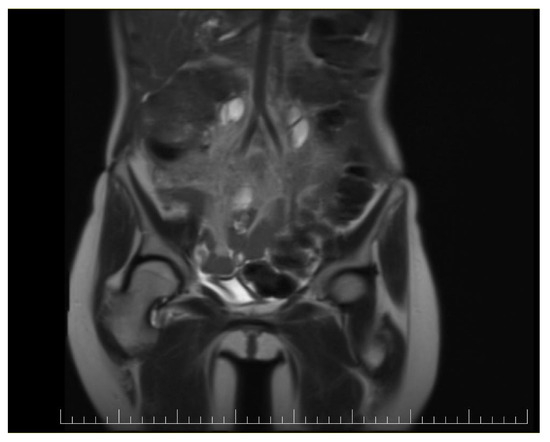

At the 3-year follow-up, the patient remains in complete remission, with no clinical or radiologic evidence of recurrence (Figure 7 and Figure 8).

Figure 7.

Postoperative coronal view of a CT image showing no signs of recurrence.

Figure 8.

Postoperative sagittal view of a CT image showing no signs of recurrence.

Periodic imaging, including contrast-enhanced CT scans, and tumor marker evaluations (CEA, CA-19-9) have consistently shown normal levels. This suggests sustained control of both peritoneal carcinomatosis and metastatic disease, demonstrating the long-term efficacy of the aggressive surgical and chemotherapeutic approach despite the severe postoperative cardiac complication [10].